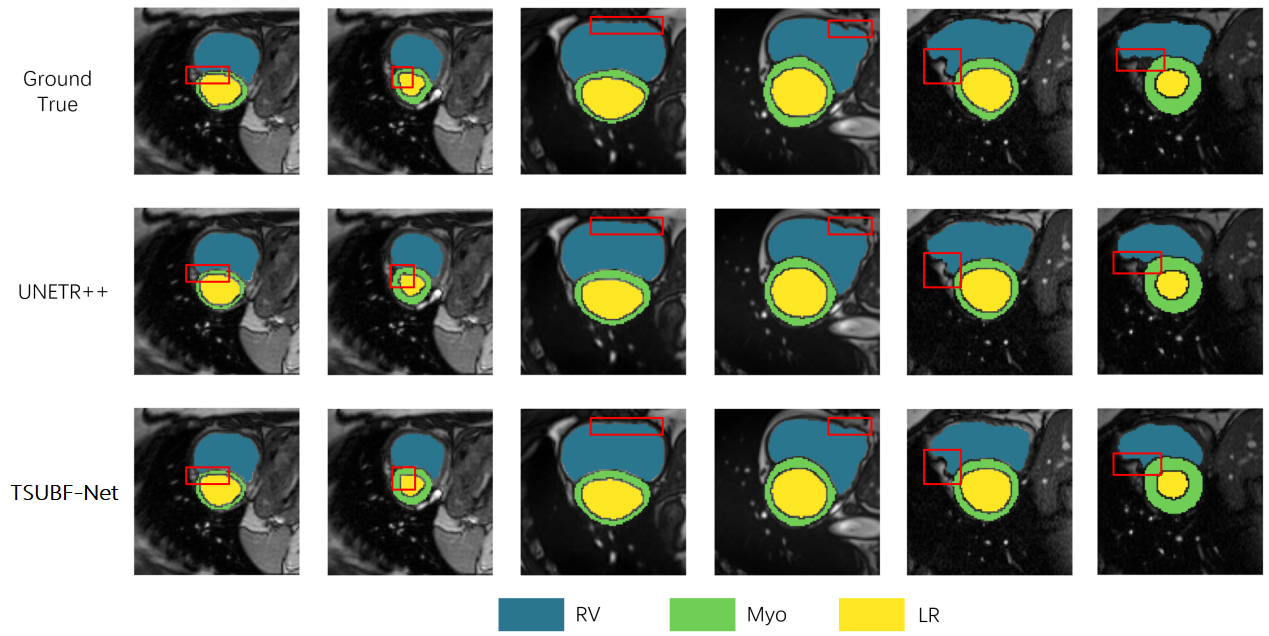

In Fig. 8, we present a qualitative comparison involving the application of our proposed TSUBF-Net to the ACDC dataset. A focused examination of the outcomes within the delineated red box reveals noteworthy insights. Although our proposed model may not exhibit exceptional performance when applied to publicly accessible organ segmentation datasets, it distinguishes itself through its remarkable capacity to generate results characterized by a superior degree of smoothness.

Furthermore, our proposed model demonstrates a particular adeptness in producing smoother predictions, particularly when the Ground Truth labels exhibit reduced inherent smoothness. Notably, UNETR++ delivers results of a comparable quality, yet our proposed model demonstrates a subtle, but discernible, edge in terms of smoothness, especially in select intricate case details. These findings emphasize the nuanced strengths of TSUBF-Net in addressing specific intricacies within the segmentation task.

Refer to caption

Figure 8: Qualitative comparison on the ACDC dataset. The red box makes it easy to see the detailed comparison of our model with the real values and UNETR++ in boundary processing.